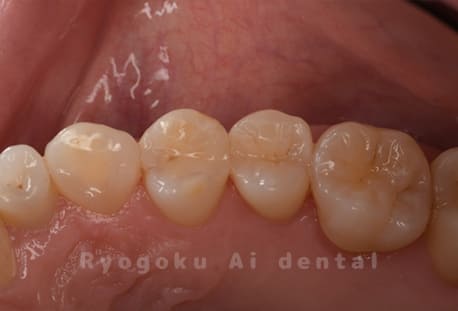

Case08

-

- 原因

- 虫歯

- 治療内容

- セラミックインレー

- 治療費用

- 77,000円

奥歯の黒い点が気になるということで来院された患者さんです。白い詰め物を外したところ、虫歯が中で大きく広がっていたため、患者さんと相談し、セラミックインレーで治療を行いました。

<リスク・副作用>

過度の咬合や衝撃で割れることがあります。